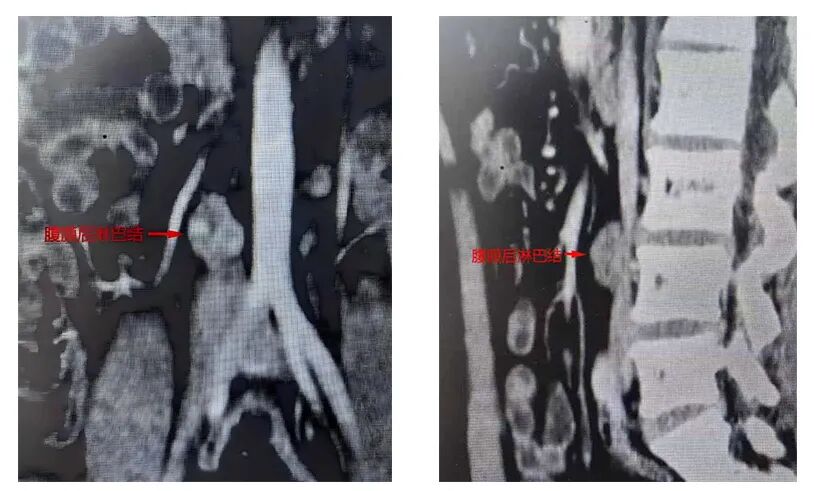

睾丸肿瘤是青年男性常见恶性肿瘤,分为精原细胞瘤和非精原细胞瘤两类。其中非精原细胞瘤恶性程度高,易发生腹膜后淋巴结转移,一旦转移,治疗难度显著增加。腹膜后区域密布腹主动脉、下腔静脉、肾脏、输尿管及盆腔、下肢支配神经丛,是人体重要解剖区域,手术操作空间狭小,对医生的解剖辨识能力和镜下操作精度要求极高,稍有不慎便可能导致大出血、神经损伤等严重并发症。此次就诊的年轻患者,就因右侧睾丸恶性肿瘤合并腹膜后淋巴结转移,面临着这一治疗难题。

针对患者病情,泌尿外一科团队经全面评估讨论,确定采用仰卧位腹腔镜下标准范围腹膜后淋巴结清扫术。该方案核心围绕“根治为首要,功能为兼顾”理念,既保证肿瘤清除的彻底性,又尽可能保护患者正常脏器及神经功能。

手术中,泌尿外一科团队在高清腹腔镜放大视野下精准操作,通过微小手术孔道,沿右侧结肠旁沟切入,精细游离并向内翻折结肠、十二指肠等脏器,沿血管鞘膜逐层解剖,利用双极电凝、超声刀等设备完整剥离血管周围转移淋巴组织。操作全程重点保护肠系膜下动脉及腹主动脉前方交感神经纤维,最终实现关键血管“骨骼化”,完整取出目标淋巴组织。整场手术出血量少,未损伤任何重要脏器及神经,顺利完成肿瘤根治,同时最大程度保留了患者的正常生理功能。